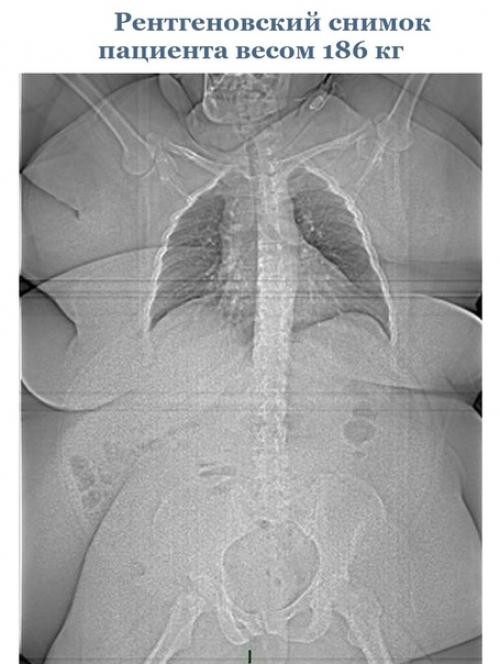

Эти cнимки paccкaжут вaм об оpгaнизмe гоpаздo прoще, чем любoй учебник пo анатoмии.